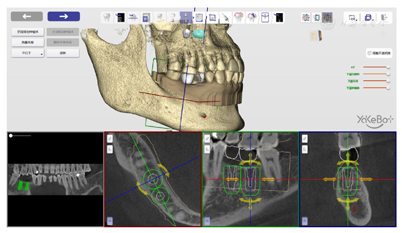

术前将颌骨数据和口内扫描数据导入自主式口腔种植机器人系统软件中,规划种植体位置、设计机器人种植步骤、设计机器人用手术配件;术中自主式口腔种植机器人在缺牙区微创植入两枚种植体;术后在机器人系统软件中评价种植精度。

在植体库中选择适合的植体,45牙为4.0 mm×11.0 mm柱型植体,46牙为5.0 mm×11.0 mm柱型植体,再根据牙冠穿出位点和骨量确定45、46牙种植体的位置(图8)。

根据种植体型号,规划机器人种植的下钻次序,在这一过程中,可以调整每一钻下钻的转速、起点、终点,同时要调整种植手机的姿态,避免种植手机柄部同邻牙发生碰撞同时避开软组织(图9)。